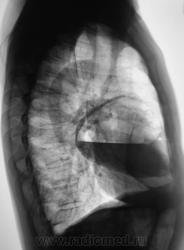

Произвели рентгенографию в стандартных проекциях.

Флюорограмма 2009 года.

сильно похоже на нагноившуюся кисту...

Она и есть.

Но, пациент жалоб не предъявляет...

Киста, точно киста. Был пациент на консультации у торакальщиков, будут готовить к плановой операции.